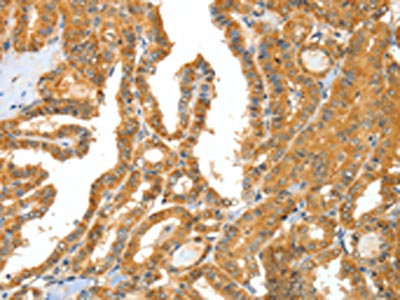

The image on the left is immunohistochemistry of paraffin-embedded Human colon cancer tissue using CSB-PA780260(APOB Antibody) at dilution 1/15, on the right is treated with synthetic peptide. (Original magnification: ×200)

The image on the left is immunohistochemistry of paraffin-embedded Human thyroid cancer tissue using CSB-PA780260(APOB Antibody) at dilution 1/15, on the right is treated with synthetic peptide. (Original magnification: ×200)